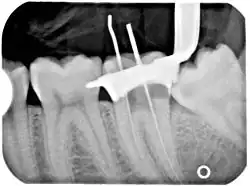

An x-ray of a root canal operation